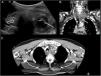

Dicho estudio se completó con ecografía y TC cervical con contraste, identificando una formación quística con extensión intratorácica que dependía del lóbulo tiroideo izquierdo (fig. 1A), con ecos internos móviles y tabiques, paredes irregulares hipercaptantes en la TC, y discontinuidad de la vertiente más caudal de la misma (fig. 1B). Además, aumento de densidad de la grasa mediastínica superior junto con adenopatías reactivas (fig. 1C). Estos hallazgos sugerían quiste tiroideo complicado con rotura y signos de mediastinitis secundaria.

A) Ecografía de cuello en modo B, donde se observa la glándula tiroides (flecha hueca) con una lesión quística con tabiques y ecos móviles en su interior dependiente de su lóbulo izquierdo (flecha fina). B y C) TC cérvico-torácica con contraste intravenoso en planos coronal (B) y axial (C). Se observa una formación de densidad quística que parece depender del polo inferior del lóbulo tiroideo izquierdo, con extensión intratorácica (flecha fina), y que condiciona desplazamiento hacia la derecha de la tráquea (asteriscos) y esófago, con engrosamiento parietal del mismo. En el margen más caudal de la lesión quística se observa discontinuidad de su pared (cabeza de flecha), en probable relación con rotura. Asocia aumento de densidad de la grasa mediastínica superior, así como adenopatías (flecha hueca), sugerentes de cambios inflamatorios mediastínicos.